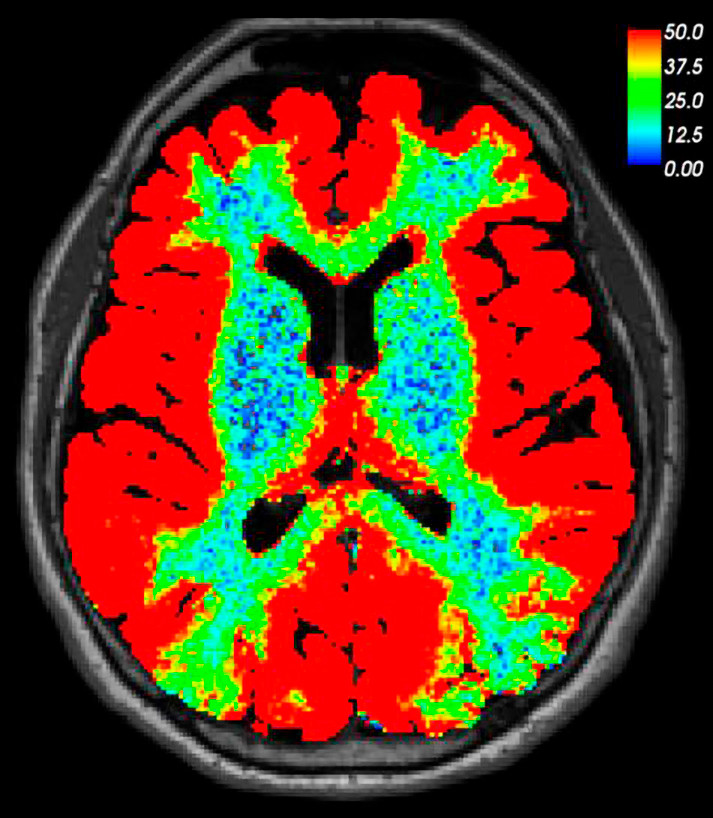

This brain MRI was taken 24 hours after lumbar puncture and intrathecal injection of an MRI contrast agent (0.5 ml gadobutrol). The patient was undergoing tests in the neurosurgical department owing to a suspected cranial cerebrospinal fluid leak. However, no leak could be detected in either the image taken after 24 hours or those that had been taken previously. In this image, which is based on T1-weighted MRI, we have used a colour scale to visualise the percentage increase in signal intensity in brain tissue as a result of contrast enhancement. The image shows that a small and water-soluble molecule like gadobutrol can produce contrast enhancement throughout the entire brain when administered via the cerebrospinal fluid. It had previously been unclear to what extent intrathecally injected drugs could enhance human brain tissue. Given that the contrast agent cannot leak into the bloodstream through an intact blood-brain barrier, we can state with certainty that the enhancement of brain tissue takes place entirely outside the blood vessels.

Since most drugs administered orally or intravenously are unable to pass through the walls of cerebral blood vessels, characterising the route into the brain from the spinal fluid could open up new possibilities for the diagnosis and treatment of brain disorders. It could also shed light on how meningeal lymphatic vessels can influence the brain via the cerebrospinal fluid (1).

Much evidence suggests that the MRI contrast agent enhances brain tissue via the so-called glial lymphatic or 'glymphatic' system, which was first described in 2012 (2). Cerebrospinal fluid acts as a transport medium for excretion of waste products such as amyloid-β and tau protein from the brain via the perivascular spaces (a form of 'brainwashing'). There is reason to believe that gadobutrol is washed out of the brain along the same route as these waste products. Glymphatic MRI has shown this excretion to be reduced in patients with a particular form of dementia (normal pressure hydrocephalus) (3).